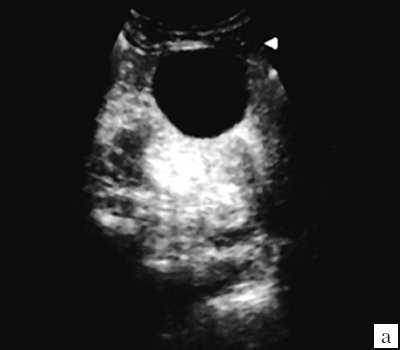

Рис. 1. Эхограмма. Кистозное образование правой почки. Гистологически - почечно-клеточная кистозная карцинома.

Многокамерное образование неправильной формы, с неровной толстой стенкой, с вкраплениями кальция, множественные перегородки с локальными утолщениями. Выраженная неоднородность внутренней эхоструктуры в виде чередования гипо-, изо- и гиперэхогеных участков.